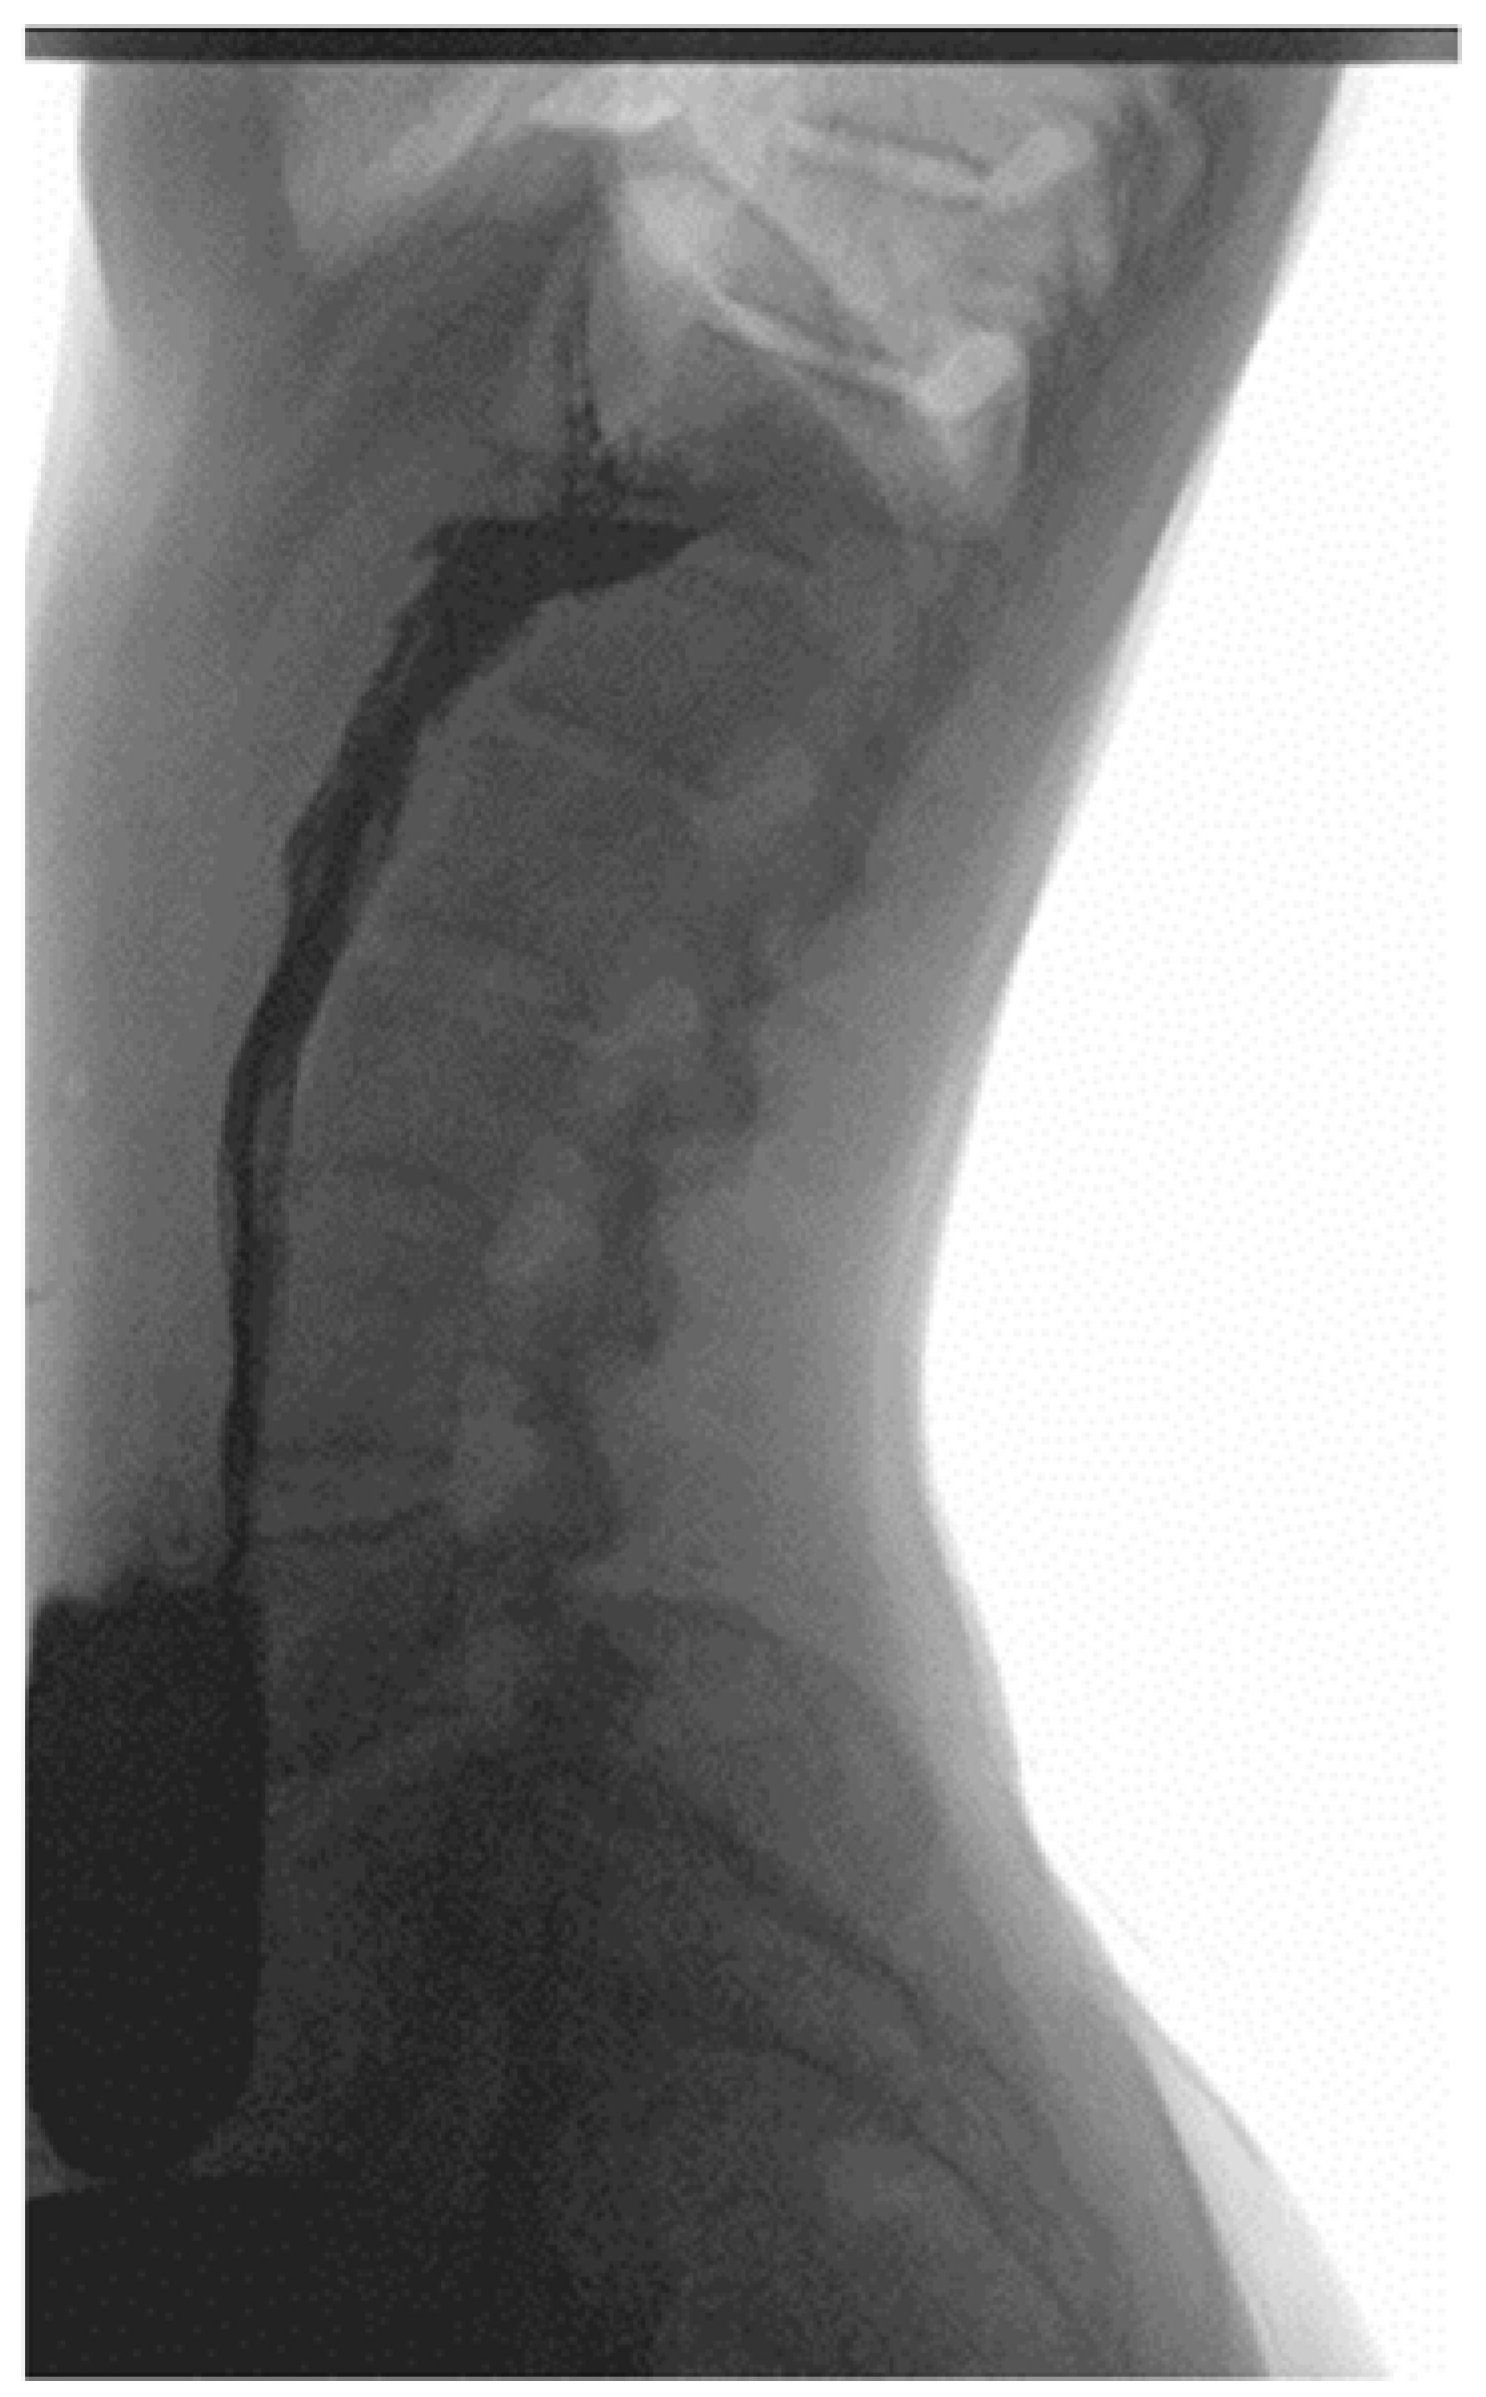

2.4. Physical Examination, Laboratory Tests’ Results and Imaging Studies

2.5. Diagnosis and Treatment